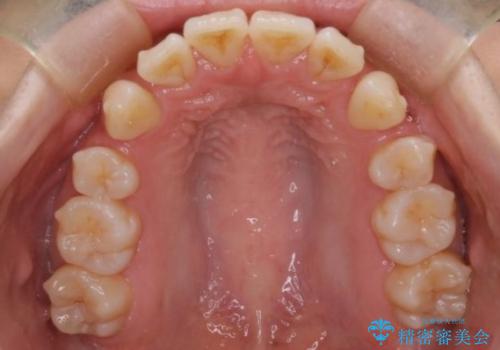

- 前歯が出ていることと、下の歯のがたがたで歯磨きがしにくいことを主訴に来院されました。

マウスピース矯正の希望があり、ワイヤーリカバリの可能性を伝えたうえでインビザライン抜歯矯正を行っています。